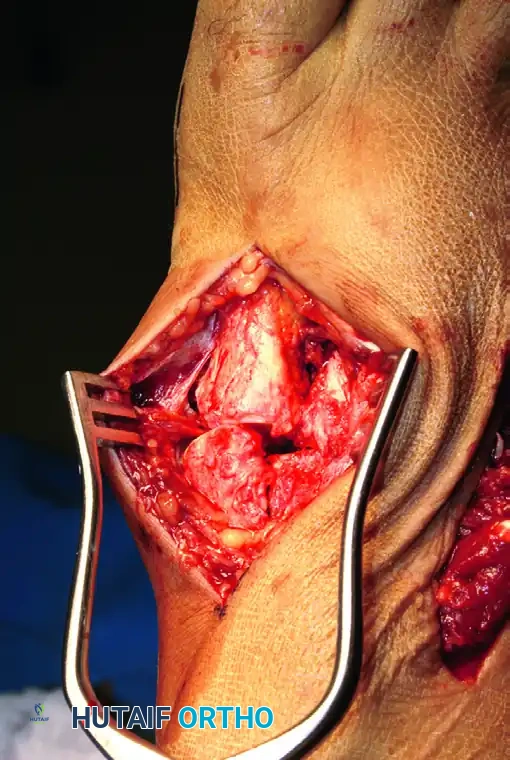

Deep Dissection and Compartment Release

- Locate and incise the inferior extensor retinaculum.

- Critical Step: Isolate the dorsalis pedis artery and the deep peroneal nerve. These structures run directly over the second TMT joint. Use a vessel loop to gently retract these structures medially or laterally. This allows safe, unhindered inspection of the Lisfranc interval.

- In cases of high-energy crush injuries, prophylactic release of the fascial compartments of the forefoot may be necessary to prevent compartment syndrome.

1. Debridement and Preparation

Remove any osteochondral debris, hematoma, or interposed soft tissue from the Lisfranc region between the base of the second metatarsal and the medial cuneiform. Failure to clear this space will preclude an anatomic reduction.